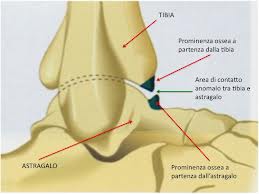

a) L’impingement anteriore è una causa comune di dolore negli atleti, in particolare giocatori di baseball, calciatori e ballerini, che sono categorie soggette a stress ripetuti durante la dorsiflessione della caviglia e a reiterati impatti nell’atto del calciare. Tuttavia si descrivono altri fattori predisponenti quali deformità congenite del piede (piede equino) e lassità del complesso legamentoso laterale, condizione che agevola la sublussazione anteriore della tibia. La sindrome è caratterizzata da rigidità e limitazione alla dorsiflessione del piede associata a dolore in sede periastragalica anteriore e a livello del mesopiede con irradiazione al malleolo laterale. Morris, che la definì “ la caviglia dell’atleta”, descrisse questa sindrome per la prima volta nel 1943. Tale condizione è riconducibile alla formazione di speroni ossei od osteofiti a livello del margine anteriore dell’epifisi tibiale e/o della superficie articolare contrapposta dell’astragalo in prossimità del collo dell’astragalo. Si tratta di proliferazioni ossee che si formano ai bordi della cartilagine articolare delle superfici dove non è applicato il carico in seguito a microtraumatismi reiterati e vanno distinte dagli osteofiti da trazione , dovuti a forze avulsive. La diagnosi si pone mediante l’esame radiologico convenzionale, eseguito in proiezione laterale e con la caviglia in dorsiflessione massima, e l’esame di Risonanza Magnetica, che su piani sagittali mostra gli stessi aspetti ed in più ci dà informazioni sulla intra od extracapsularità dell’osteofita.

Utile è la valutazione dei rapporti con i tessuti molli adiacenti, in particolare la capsula articolare, al fine di pianificare il successivo trattamento, che consiste nella resezione artrotomica o artroscopica delle formazioni ossee; questo porta alla regressione del dolore ed al recupero della funzionalità articolare.

b) L’impingement antero-laterale si osserva a livello di un recesso sinoviale localizzato tra tre strutture ossee: tibia, fibula e astragalo; tale area anatomica è delimitata anteriormente dal legamento tibio-peroneale antero-inferiore e dal legamento peroneo-astragalico anteriore, ed inferiormente dal legamento peroneo-calcaneale. La sindrome è caratterizzata da dolore cronico in sede laterale esacerbato durante l’eversione o la dorsiflessione del piede, e dal salto su un piede. L’esame clinico documenta dolore nella regione antero-laterale del piede e tumefazione nelle fasi più avanzate. L’impingement può essere causato da un solo trauma o da microtraumi ripetuti. La distorsione di caviglia è universalmente considerata uno dei più comuni traumi osservati; si ha soprattutto durante l’attività sportiva ed è più frequente soprattutto nei giocatori di basket e nei calciatori, e nella maggior parte dei casi si tratta di pazienti che hanno meno di 35 anni. Nell’85% dei casi, l’evento traumatico si ha in inversione e coinvolge il complesso legamentoso laterale, nel quale il legamento più facilmente colpito è il legamento peroneo-astragalico anteriore.

Il trattamento conservativo porta alla guarigione senza complicanze nella maggior parte dei casi; tuttavia si è stimato che circa il 3% delle distorsioni di caviglia può portare ad una sindrome da impingement antero-laterale. Un trauma in inversione con almeno una lesione parziale del legamento talo-fibulare anteriore può determinare un danno con conseguente reazione infiammatoria della sinovia a livello dell’interlinea articolare antero-laterale. In assenza di un adeguato trattamento di immobilizzazione o di riabilitazione, può aversi ipertrofia e fibrosi cicatriziale a livello della sinovia. La cronicizzazione di questi fenomeni può portare allo sviluppo di una proliferazione che si estende nel recesso antero-laterale e che causa impingement meccanico e dolore. Più raramente questa massa può determinare l’erosione della porzione antero-laterale del domo astragalico, con conseguente sviluppo di foci di condromalacia. Oltre all’ispessimento ed alla deformità cicatriziale del legamento tibio-fibulare anteriore, la RM eseguita su piani di scansione assiali e sagittali, mostra, soprattutto in presenza di versamento intra-articolare, un’intensità di segnale intermedia del tessuto sinoviale sia nelle sequenze T1 che T2 pesate . RM ed artro-RM, soprattutto in presenza di versamento intra-articolare, sono in grado di documentare sia l’ipertrofia sinoviale, causa di impingement antero-laterale, che eventuali lesioni cartilaginee, ossee e legamentose associate.